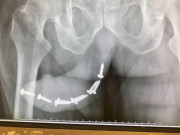

Bác sĩ dẫn trường hợp bệnh nhân nam 24 tuổi sở hữu chiều cao 160cm, đến khám vì lý do “cậu nhỏ” còn quá bé. Khi đó, “cậu nhỏ” của anh chàng này chỉ như một cậu bé 10 tuổi. Điều này khiến anh chàng có yêu một vài người nhưng rồi các bạn gái đều lẳng lặng bỏ anh đi. Anh rơi vào bế tắc, tuyệt vọng… và dần trở nên “ghét” phụ nữ. Sau khi, khám và xét nghiệm bệnh nhân được chẩn đoán là suy sinh dục thứ phát.

Qua quá trình điều trị khoảng 6 tháng “cậu nhỏ” của chàng trai này đã phổng phao lên như cậu bé 14 tuổi. Sau một năm thì “cậu nhỏ” của chàng này đã phát triển hoàn toàn như người trưởng thành bình thường (có tinh trùng, dương vật to và dài thêm được 5cm, lông mu lông nách, râu ria đã đen và dài).

Điều đặc biệt là chiều cao của chàng trai này đã tăng thêm 8cm khá ấn tượng, từ 160cm đã lên 168cm.